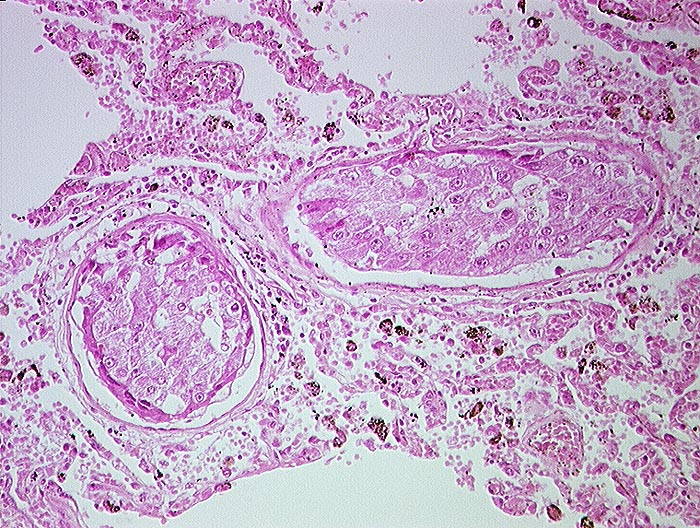

AP/ Hepatozelluläres Karzinom: Lungenmetastasen

Hepatozelluläres Karzinom: Lungenmetastasen

Lunge, Mediastinum mit Thymus

Lunge